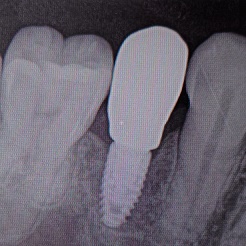

差し歯

こんにちは。葛飾かもめ歯科です。

当院で力を入れている分野は差し歯(人工の歯)です。

保険を使った歯でも、技術の優れた技工士さんが丁寧に本物と見分けがつかないほどに仕上げております。

一般歯科、小児歯科、歯周病、予防歯科、審美歯科、ホワイトニング、歯科口腔外科、義歯(入れ歯)、インプラント、矯正歯科